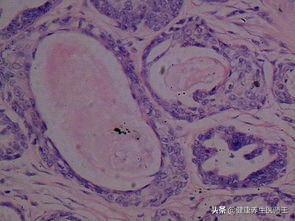

平滑肌瘤 来源于外阴平滑肌、毛囊立毛肌或血管平滑肌。多见于生育年龄妇女,常位于大阴唇、阴蒂及小阴唇。质硬,表面光滑,突出于皮肤表面。镜下见平滑肌细胞排列成束状,与胶原纤维束纵横交错或形成漩涡状结构,常伴退行性变。治疗原则为肌瘤除术。